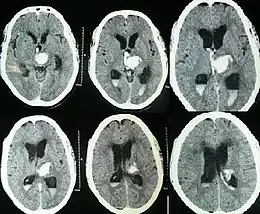

| Hydrocephalus as seen on a CT scan of the brain. The black areas in the middle of the brain (the lateral ventricles) are abnormally large and filled with fluid. | |